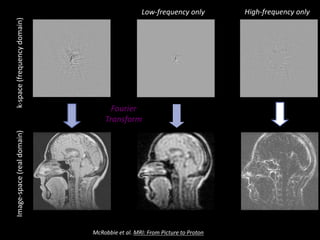

Figure 7.10 Images and their 2D spectra (k-space) showing: (a) reconstruction from all spatial frequencies, (b) low spatial

(a) (b) (c)

k-space	(frequency	domain)Image-space	(real	domain)

Fourier

Transform

Low-frequency	only High-frequency	only

McRobbie et	al.	MRI:	From	Picture	to	Proton